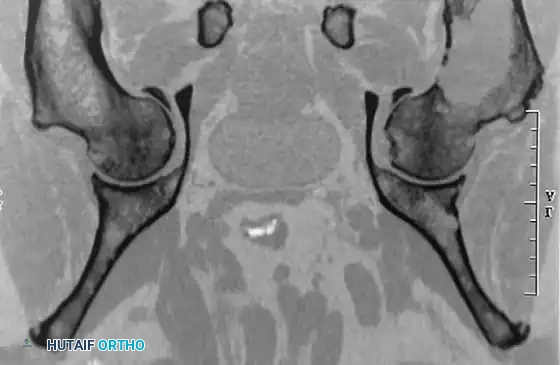

Image

Anteroposterior and lateral radiographs of the proximal femur of a 61-year-old man with multiple myeloma showing multiple lytic lesions.